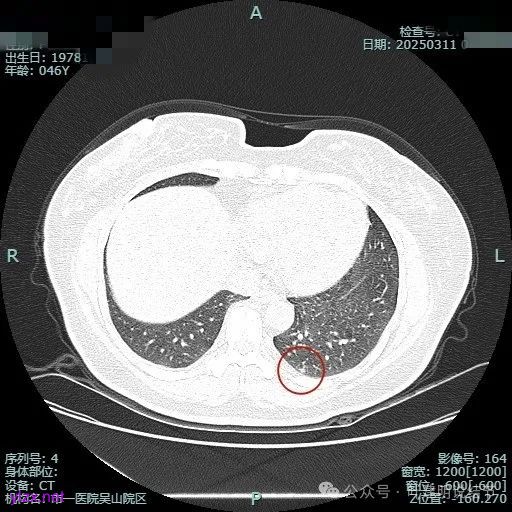

我们先来看2024年9月时的影像:

病灶1:

右下背段混合密度病灶,边上不太清爽,有片状淡磨玻璃影,实性部分密度较高。

感觉病灶有点晕征似的,表面不平,灶内不太致密。

有小血管进入,似有晕征。

离胸膜近但牵拉不明显,病灶边缘有细毛刺,较短且不太锐利。

边缘少许磨玻璃成分,血管进入明显。

瘤肺边界稍显不清。

病灶2:

右中叶内侧段可见混合密度结节,大部分实性,形态与下叶背段的类似。

病灶3:

左下叶基底段微小结节,也是混合密度偏实性,瘤肺边界稍不清,与右侧的是类似形态的。